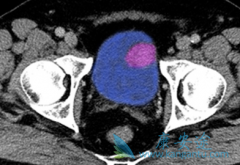

阿比特龙 (Zytiga)是前列腺癌靶向药,在服用之前必需先化疗吗?在以往的试验当中,前列腺癌患者用过多西他赛化疗后,服用阿比特龙取得了良好的治疗效果。但如果没有用多他西塞化疗的患者使用阿比特龙会有怎么样的结果呢?   2015年LANCET ONCOL又发 ...

• 试验证明联合阿比特龙(Abiraterone)无法克服恩杂鲁胺耐药

试验证明联合阿比特龙(Abiraterone)无法克服恩杂鲁胺耐药

恩杂鲁胺耐药可能是由雄激素升高引起的,并可通过联合醋酸阿比特龙来克服。但一项随机、双盲、安慰剂对照设计的PLATO研究发现,恩杂鲁胺单药治疗期间PSA进展后应用恩杂鲁胺联合醋酸 阿比特龙 (Abiraterone)和强的松并未显示(上述假说中的结果)。研究 ...